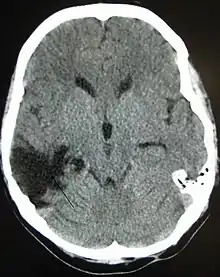

Ушкодження мозку, нейротравма або мозкова травма — це руйнування або дегенерація клітин мозку. Ушкодження мозку може статися із багатьох причин зовнішнього характеру. У загальному випадку, пошкодження мозку відноситься до значних, недискримінаційного пошкодження, викликаного травмою, в той час як селективне пошкодження нейронів хімічними речовинами називають нейротоксичністю.

Це поняття є загальним для великої кількості різного типу ушкоджень таких як Черепно-мозкова травма (ЧМТ), що є наслідком фізичної травми або травми голови від зовнішнього фактору, і терміну Надбане ушкодження мозку, що використовується у певних контекстах, аби відрізнити ушкодження мозку, які виникають після Народження від травм, генетичних порушень, або від вад розвитку.[1]